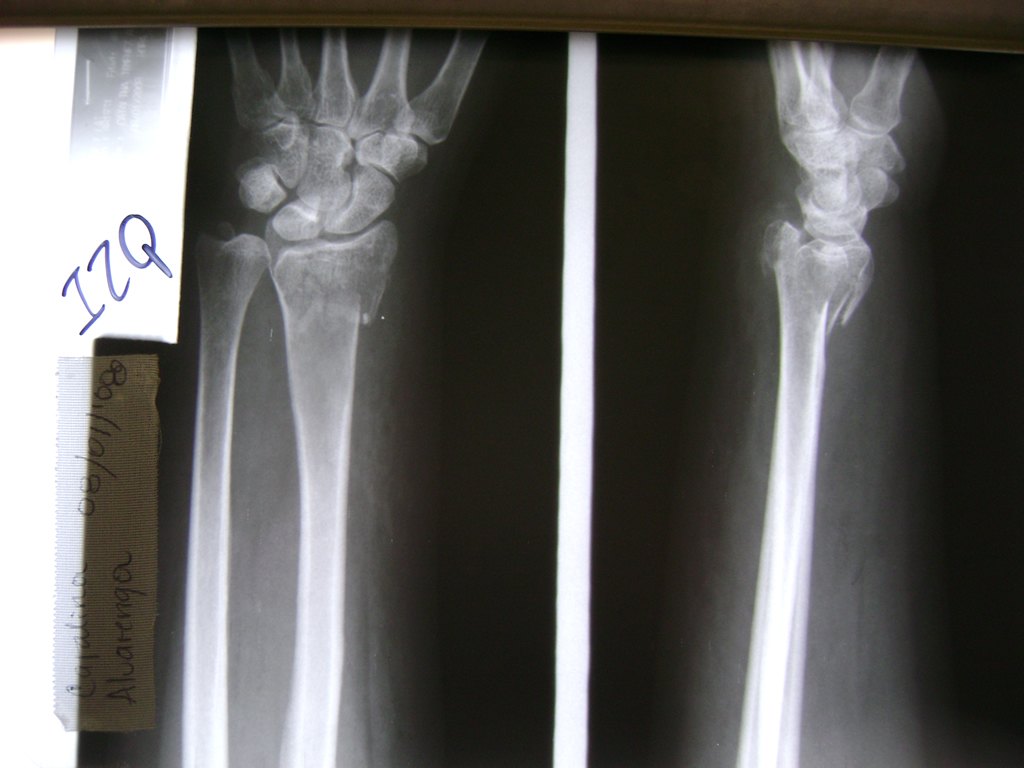

Cirugía de Fémur - Cirugías de Muñecas y Manos

Los procedimientos más comunes en cirugía de la mano son aquellos destinados a reparar traumatismos, incluyendo lesiones de tendones, nervios, vasos sanguíneos, y articulaciones; huesos fracturados; y quemaduras, cortes, y otros daños de la piel.